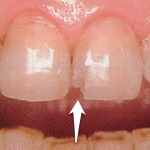

| 症例 3 | |

|---|---|

| 症例2同様、変色したレジンの再治療です。 レジン治療は保険適用。治療のための通院回数は1回です。 | |

| Before | After |

![]() | ![]() |

| レジン表面の色が変色しています | 周囲の色と同じ色調に改善されました |